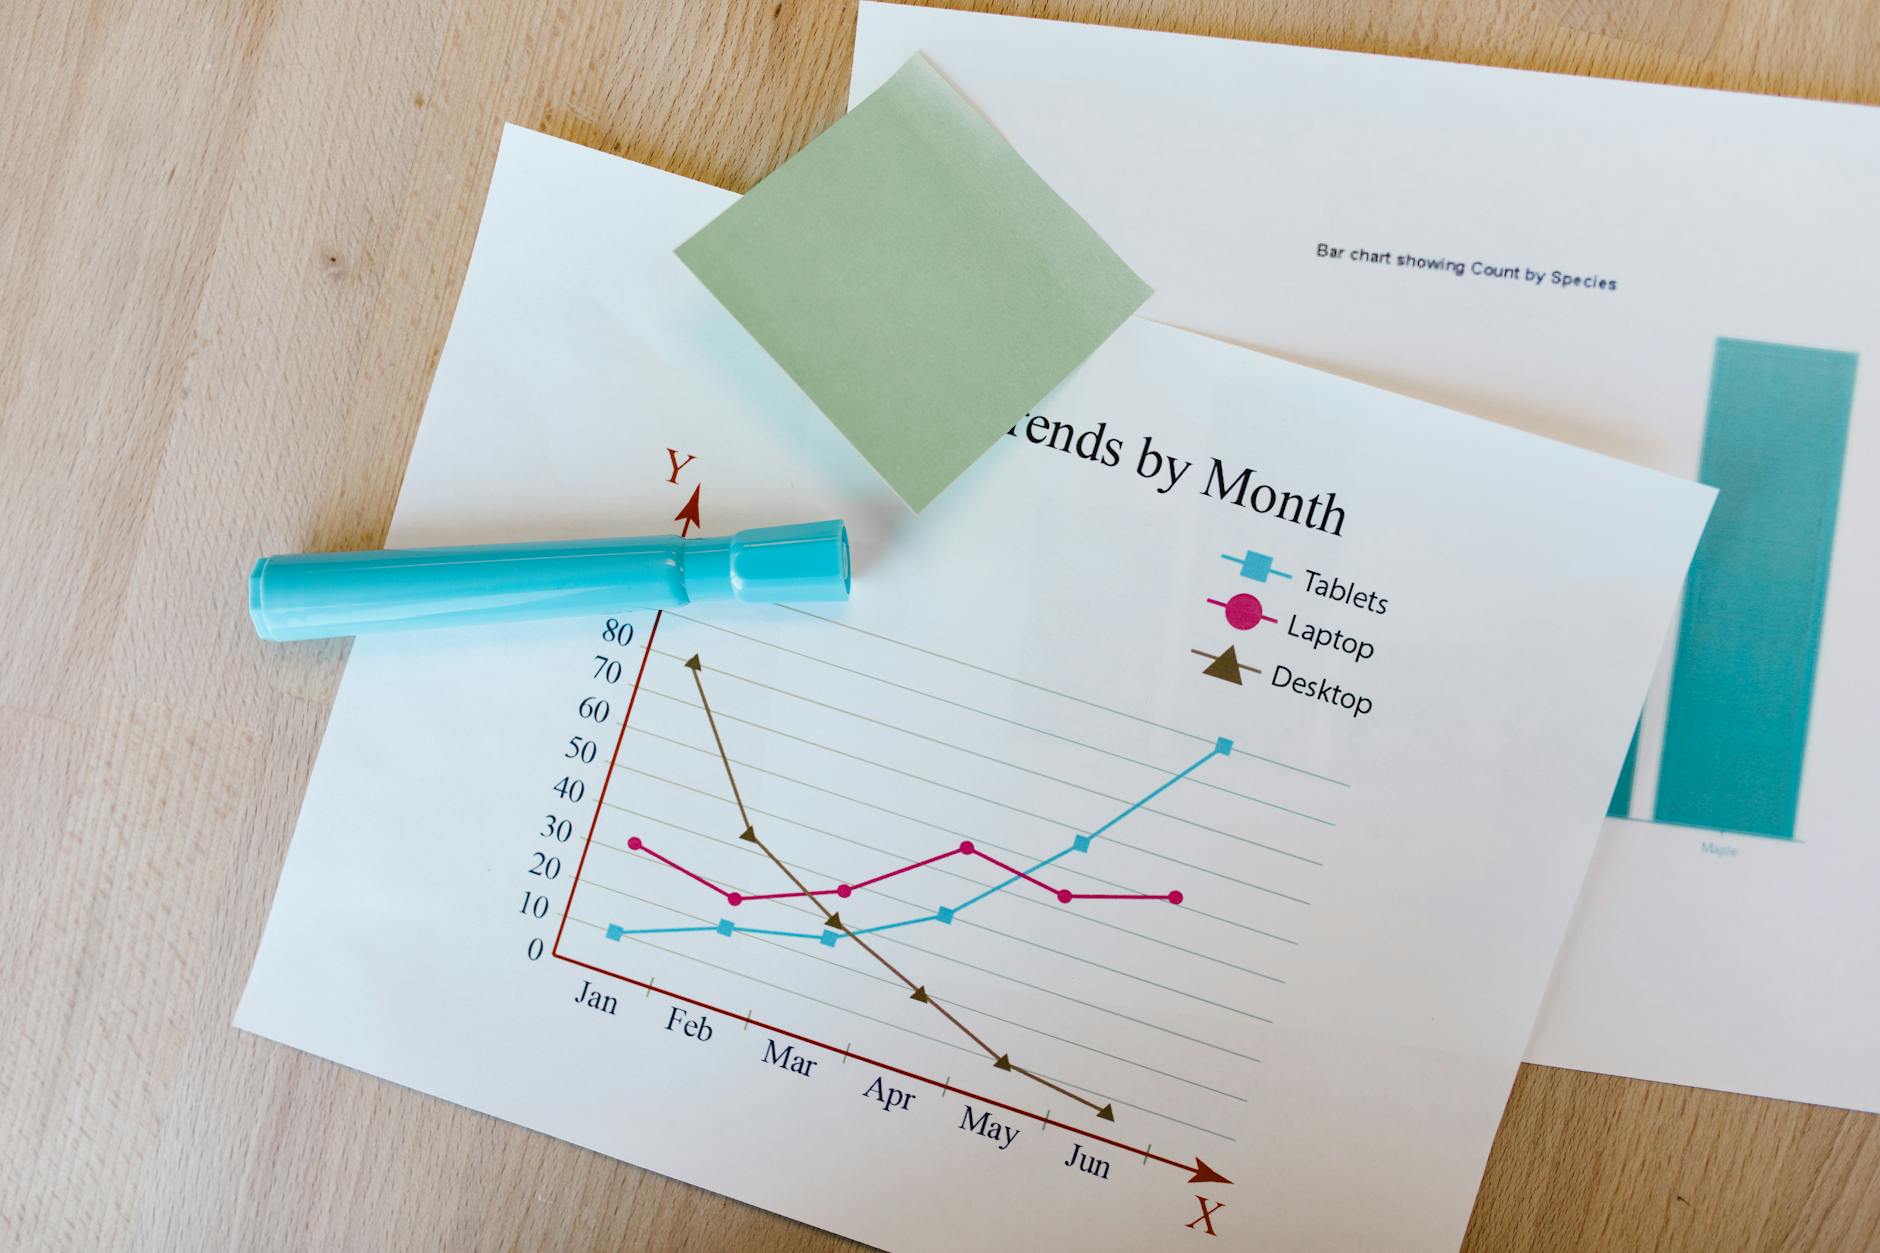

Wiele osób miesza te pojęcia. Powinowactwo wiązania (Ki) i aktywność funkcjonalna (EC50, Efficacy) to nie to samo. Ki mierzy, jak mocno substancja wiąże się z receptorem – niższe oznacza silniejsze. EC50 wskazuje stężenie, przy którym występuje 50% maksymalnego efektu. A Efficacy mówi, jak silny jest efekt maksymalny w porównaniu do serotoniny.

Dla 4-PrO-DMT – najbliższego analoga 4-PrO-MET z opublikowanymi danymi – ujawnia się instruktywny wzorzec. Powinowactwo wiązania do 5-HT2A? Z Ki = 336 nM jedynie umiarkowane. Ale Efficacy wynosi 93–104%. 4-PrO-DMT nie wiąże się zatem szczególnie mocno z receptorem, jednak aktywuje go niemal tak sprawnie jak sama serotonina.

The numbers are revealing. 4-PrO-DMT showed a 5-HT2A binding affinity of Ki = 336 nM – moderate by tryptamine standards. Its functional activity told a different story: EC50 values of 3-93 nM with 93-104% efficacy at 5-HT2A, making it a near-full to full agonist. The head-twitch response ED50 in mice came in at 0.31 mg/kg (subcutaneous), and the selective 5-HT2A antagonist M100907 blocked it completely. That's clean confirmation of 5-HT2A mediation.

Comparing 5-HT2A Profiles Across Tryptamines